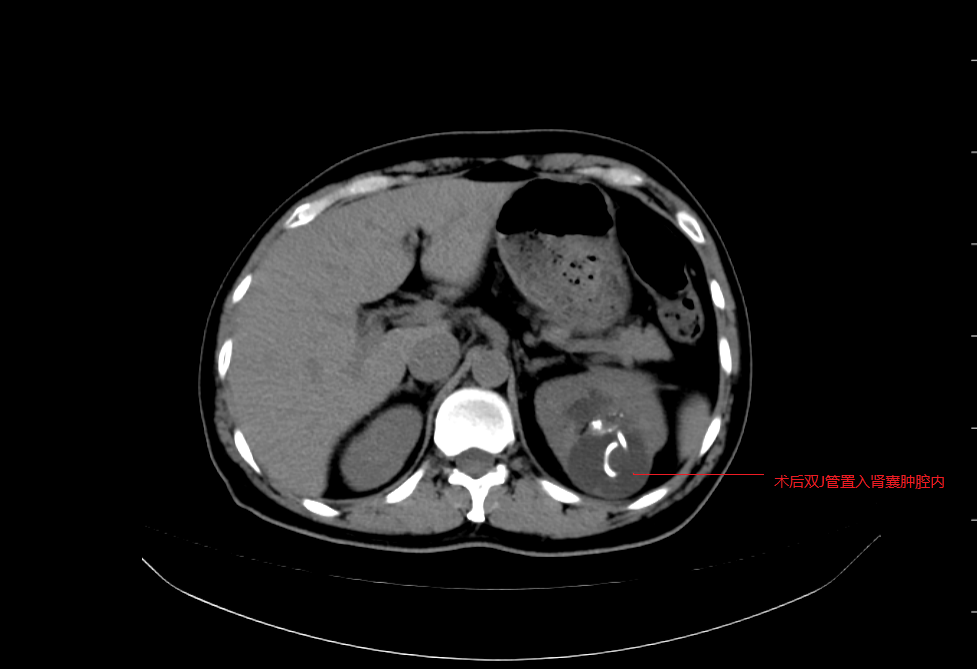

本以为是普通的腰疼,没想到检查发现左肾里竟同时藏着“结石”和“大囊肿”两个隐患。近日,一名47岁的男性患者在阳山县人民医院泌尿外科接受了左输尿管软镜下钬激光碎石取石术,同时通过经尿道输尿管软镜下肾囊肿内切开引流术,一次手术解决了两个棘手问题。术后患者恢复迅速,已顺利出院。 体检发现“双雷”埋伏 47岁的张先生(化名)最近因腰部不适来我院就诊。原本以为只是劳累所致,没想到B超和CT检查结果却让他大吃一惊:他的左肾不仅有多发结石,还长了一个巨大的肾囊肿。 这种情况在临床上并不少见,但同时处理起来却颇为棘手。泌尿外科医生介绍,传统的治疗方案往往需要“分步走”:要么先通过经皮肾镜(在腰上打孔)处理结石,后期再处理囊肿;要么通过腹腔镜手术“剥”掉囊肿,但对结石却难以兼顾。这意味着患者可能要经历两次手术、两次麻醉,不仅身体创伤大,恢复周期长,也增加患者经济负担。 巧妙设计:“借道”尿道,一箭双雕 考虑到患者年仅47岁,对生活质量要求高,且非常希望避免在身体上留下多处疤痕,我院泌尿外科团队经过详细的术前讨论,决定为其实施输尿管软镜下的一期手术。 这个手术的奥妙在于“借道而行”。医生利用人体天然的泌尿系统腔道——尿道,将纤细灵巧的输尿管软镜送入肾脏。 1. 先碎石: 抵达左肾后,医生首先发现了那些“捣乱”的结石。通过软镜的工作通道,插入钬激光光纤,将结石精准击碎成粉末状或小碎片,较大的碎片可直接用套石篮取出 。 2. 后开窗: 碎石完成后,镜头一转,找到了那个压迫肾实质的囊肿。在软镜的直视下,医生换用钬激光在囊肿壁最薄、最靠近肾集合系统的位置切开一个“小窗”,让囊液能够顺畅地流入肾盂,顺着尿液排出体外,从而达到内引流减压的目的 。 就这样,一根软镜,两种操作,患者腰上的两颗“雷”被一次性安全拆除。 微创领域的“黑科技” 输尿管软镜技术被誉为泌尿外科医生的“第三只眼”。其头端可以 270度弯曲,能轻松到达肾脏的各个角落,处理传统硬镜无法触及的结石和病变 。 而将其应用于肾囊肿内切开引流,更是近年来微创理念的延伸。相比于传统的腹腔镜或开放手术,这种术式拥有无可比拟的优势 : 真正无痕: 手术完全经自然腔道进行,体表没有任何切口,满足了现代患者对美观的需求。 同期治疗: 如张先生这般,可以一次麻醉处理多个合并疾病,避免了二次住院的麻烦。 恢复迅速: 由于手术创伤极小,患者术后疼痛轻。文献数据显示,此类手术患者术后住院天数通常仅为3天左右 。张先生术后恢复顺利,很快便康复出院。 术后康复与新生活的开始 术后,张先生的腰部胀痛感明显缓解。复查显示,左肾结石已清理干净,囊肿也已成功“瘪”了下去。他感慨地说:“原本以为要在身上打两个洞,甚至做两次手术,没想到睡一觉起来,两个问题都解决了,身上连个创可贴都没贴。” 此次手术的成功,标志着我院泌尿外科在处理肾脏复合性疾病方面迈上了新台阶。我们也将继续探索和运用更先进的微创技术,让更多的患者能享受到“损伤小、恢复快、效果佳”的优质医疗服务。 门诊地址:门诊楼2楼泌尿外科诊室 住院部地址:外科楼(5号楼)9楼 联系电话:0763-7816525 杨竞锋 主任医师 阳山县人民医院泌尿外科主任,主任医师。广州医科大学临床医学专业毕业,1993年7月参加工作。从事大外科临床工作10余年,泌尿外科专科工作10余年。曾多次在广州市三甲医院进修泌尿外科专业。擅长尿路结石及良性前列腺增生微创治疗,熟练开展前列腺整体剜除术等四级手术,临床经验丰富。现任清远市医学会泌尿外科分会常务委员,清远市医学会男科分会委员,广东省泌尿生殖尿控分会委员。曾主持市级课题2项,以第一作者或通讯作者发表论文近10篇。 封长其 副主任医师 阳山县人民医院泌尿外科副主任,副主任医师,医学学士,2008年毕业于贵州医科大学临床医学系。从事泌尿外科临床、教学工作10余年,2018年到广东省第二人民医院泌尿外科进修,以第一作者发表省级医学论文多篇,擅长泌尿系结石、前列腺增生的微创手术,擅长泌尿外科常见开放手术治疗,熟悉泌尿外科腹腔镜手术,对泌尿外科急危重患者管理积累了丰富的经验。对泌尿外科肿瘤(如肾癌、膀胱癌、前列腺癌、肾上腺肿瘤)以及泌尿系畸形的治疗及手术亦积累了较多经验。 陈宇航 副主任医师 阳山县人民医院泌尿外科副主任医师,科室技术骨干,广州医学院临床医学本科,2001年7月参加工作,擅长泌尿外科常见病、多发病诊治及微创手术。